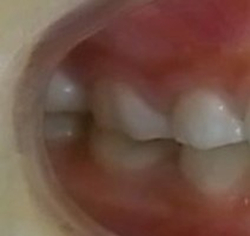

今回は、歯並びが悪く、顎が小さいお子様の症例です。

矯正前 矯正後

今回も治療には、独自の方法とビムラー装置等を利用しました。

咬合バランスをよくする為には、

顎を大きくするだけでは不十分と考えています。

その為、かみ合わせの高さなどを立体的に改善していく事を心がけて治療しています。